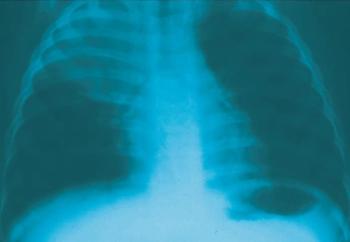

Respiratory symptoms are a major reason why outpatients seek medical care, and primary care physicians who treat children frequently see pneumonia. This week’s photo essay tests your knowledge of respiratory problems in kids.

Pneumonia is one of the most common conditions encountered by primary care providers. Certain organisms cause pneumonia in particular age groups. For example, group B streptococci, Gram-negative bacilli Escherichia coli in particular) and, rarely, Listeria monocytogenes cause pneumonia in neonates. In infants younger than 3 months, group B streptococci and organisms encountered by older children occasionally cause pneumonia, as does Chlamydia trachomatis. Older infants and preschoolers are at risk for infection with Streptococcus pneumoniae and Haemophilus influenzae. In children older than 5 years, S pneumoniae and Mycoplasma pneumoniae are the key pathogens. Let the patient's age, history, clinical presentation, and radiographic findings guide your choice of therapy. Even though most patients with uncomplicated pneumonia can be treated as outpatients, close follow-up is important. Hospitalize patients younger than 6 months and those with complications.